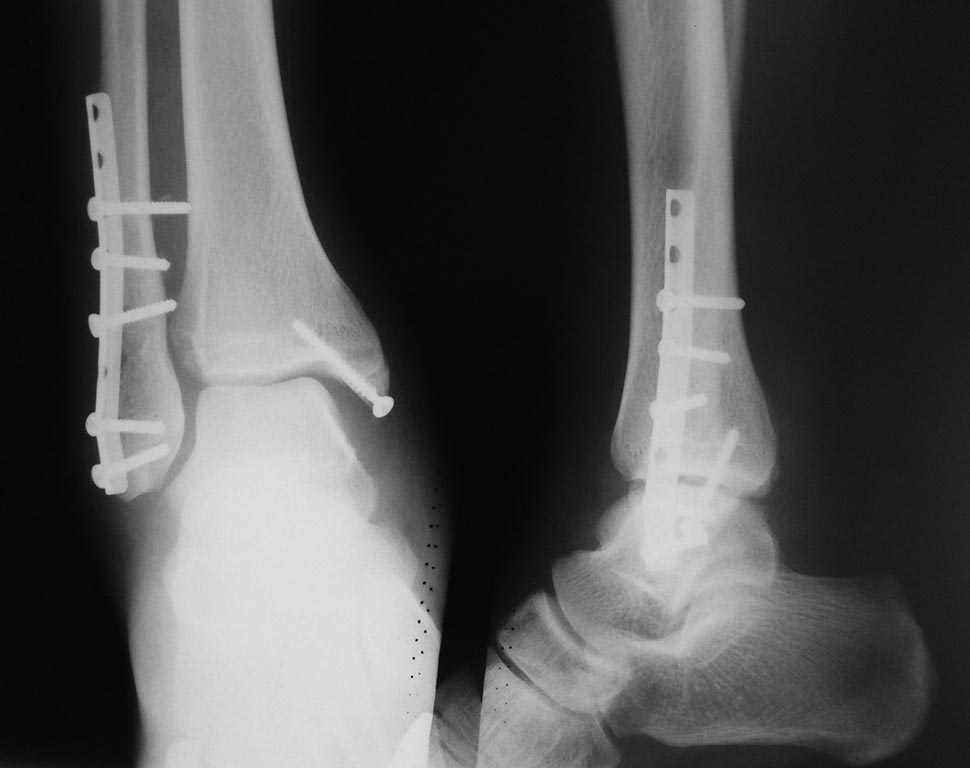

[Ortho] Разрыв межберцового синдесмоза

Здравствуйте коллеги, во время операции не смог поставить позиционный винт.

В данном случае что делать?Дальнейшая тактика лечени ? Какие последствия

могут быть?Спасибо